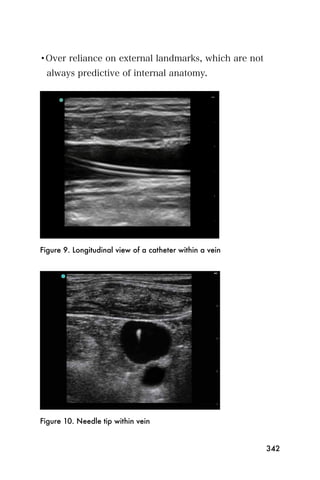

center that is the endometrium.

Figure 3. The bladder (*) and empty uterus (arrow)

An empty uterus may cause the clinician to worry about

an ectopic pregnancy. A ruptured ectopic pregnancy

blood may extend into the abdomen, so it is important

107

to look for blood within the abdomen as well as the

pelvis. The sonographer can begin imaging the area

between the liver and the kidney on the mother s right

side. This is the same window that is used to look for